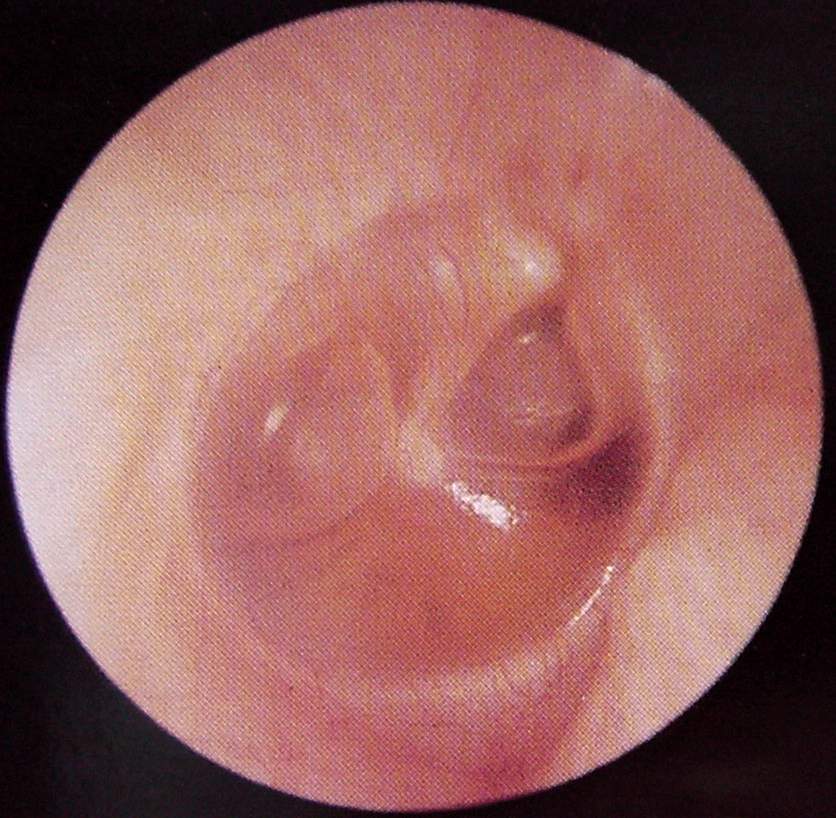

Ear Clinical Photos for Static Stations